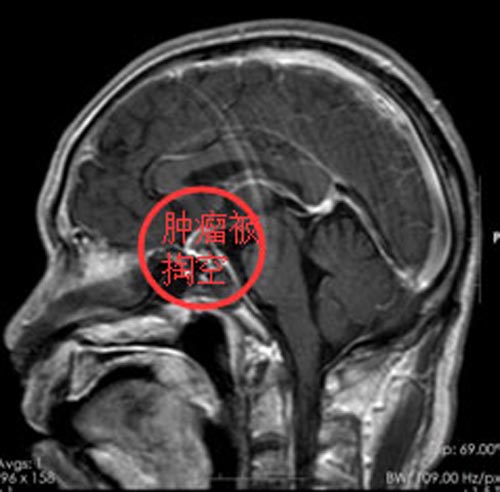

考虑患者病情比较严重,肿瘤巨大,侵犯了大脑鞍区,蝶窦等部位,手术难度非常高。充分准备后,由鲁明副院长、邓心情医生在全麻下行内镜经鼻蝶鞍区占位切除术,术中特别注意保护相邻的颈内动脉,大脑前,大脑中动脉,海绵窦,脑深部引流静脉等血管结构,保护相近的颅神经,脑干,垂体炳,下丘脑,皮层功能区,基底节,丘脑等结构,前颅底重建,避免脑脊液漏。术程顺利,术后一周,程叔头痛头晕症状消失,视力好转,无重影现象,无并发症出现,已康复出院。

▲手术后